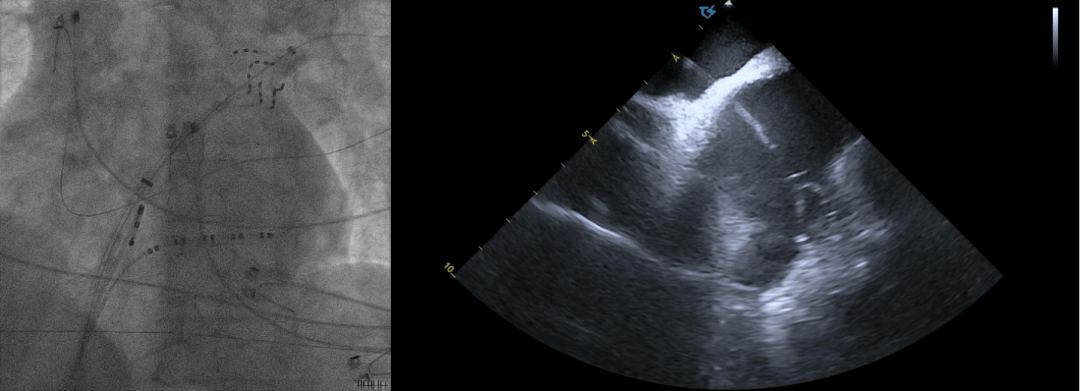

ICE引导下房间隔穿刺:

术中ICE指引导丝到上腔静脉

ICE直视下进行房间隔穿刺

穿刺后打水确认